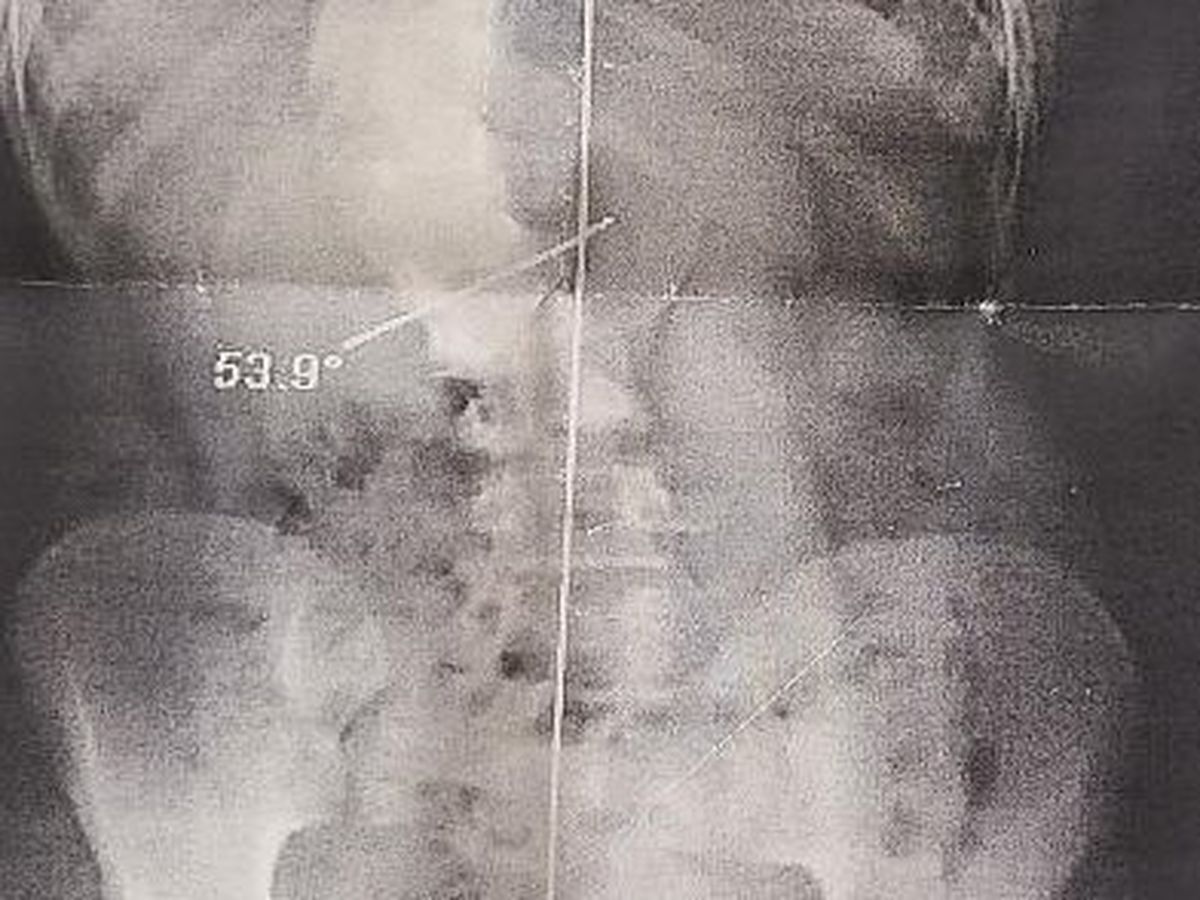

Yep, that's Mazie's spine! But it will look much better in October!!!

Unfortunately Mazie has been diagnosed with severe double scoliosis (curvature of the spine in two places) and kyphosis (excessive outward curvature of the spine) and her doctors have attempted everything possible to help to straighten her back including braces and physical therapy. Despite their best efforts, her condition has worsened and she has to have spinal fusion surgery followed by an extensive recovery period.